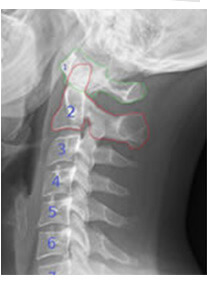

その秘密はアトラス(頸椎1番)にありました。

重い後頭骨の真下にあるアトラスは全身の歪みが集中する場所であり、その矯正効果の高さから「カイロの神髄」とも呼ばれている部位です。

脳からの神経伝達が正常に伝わらないと、患者さんの主訴である、慢性的腰痛、肩こり、頭痛、背中痛、自律神経の乱れ、不定愁訴など、様々な不調が起こることは言うまでもありません。

アトラスにズレが生じると、脳からの神経伝達がシャットアウトされて、全身の機能が正常に働かなくなってしまいます。

それほど重要な部位ですので、アトラス1つ治すことができれば当然、身体全体の機能が一気に正常化します。主訴が消えるだけではありません。患者さんの身体が治癒力を取り戻し、ほかの部位の矯正では得られない劇的な結果を出すことができるのです。

三浦先生はこのゴルジ腱器官の反射を利用し、頸部にある一定の刺激を与えることで頸骨と頸骨を繋ぐ筋肉を弛緩させ、アトラスのズレを正確に矯正することに成功しました。

このテクニックを使うと、わずか数秒頸部に触れているだけで、勝手に頸骨が動き出します。

あとは「カコッ…」とアトラスが本来の位置に収まるのを待つだけで、施術終了です。